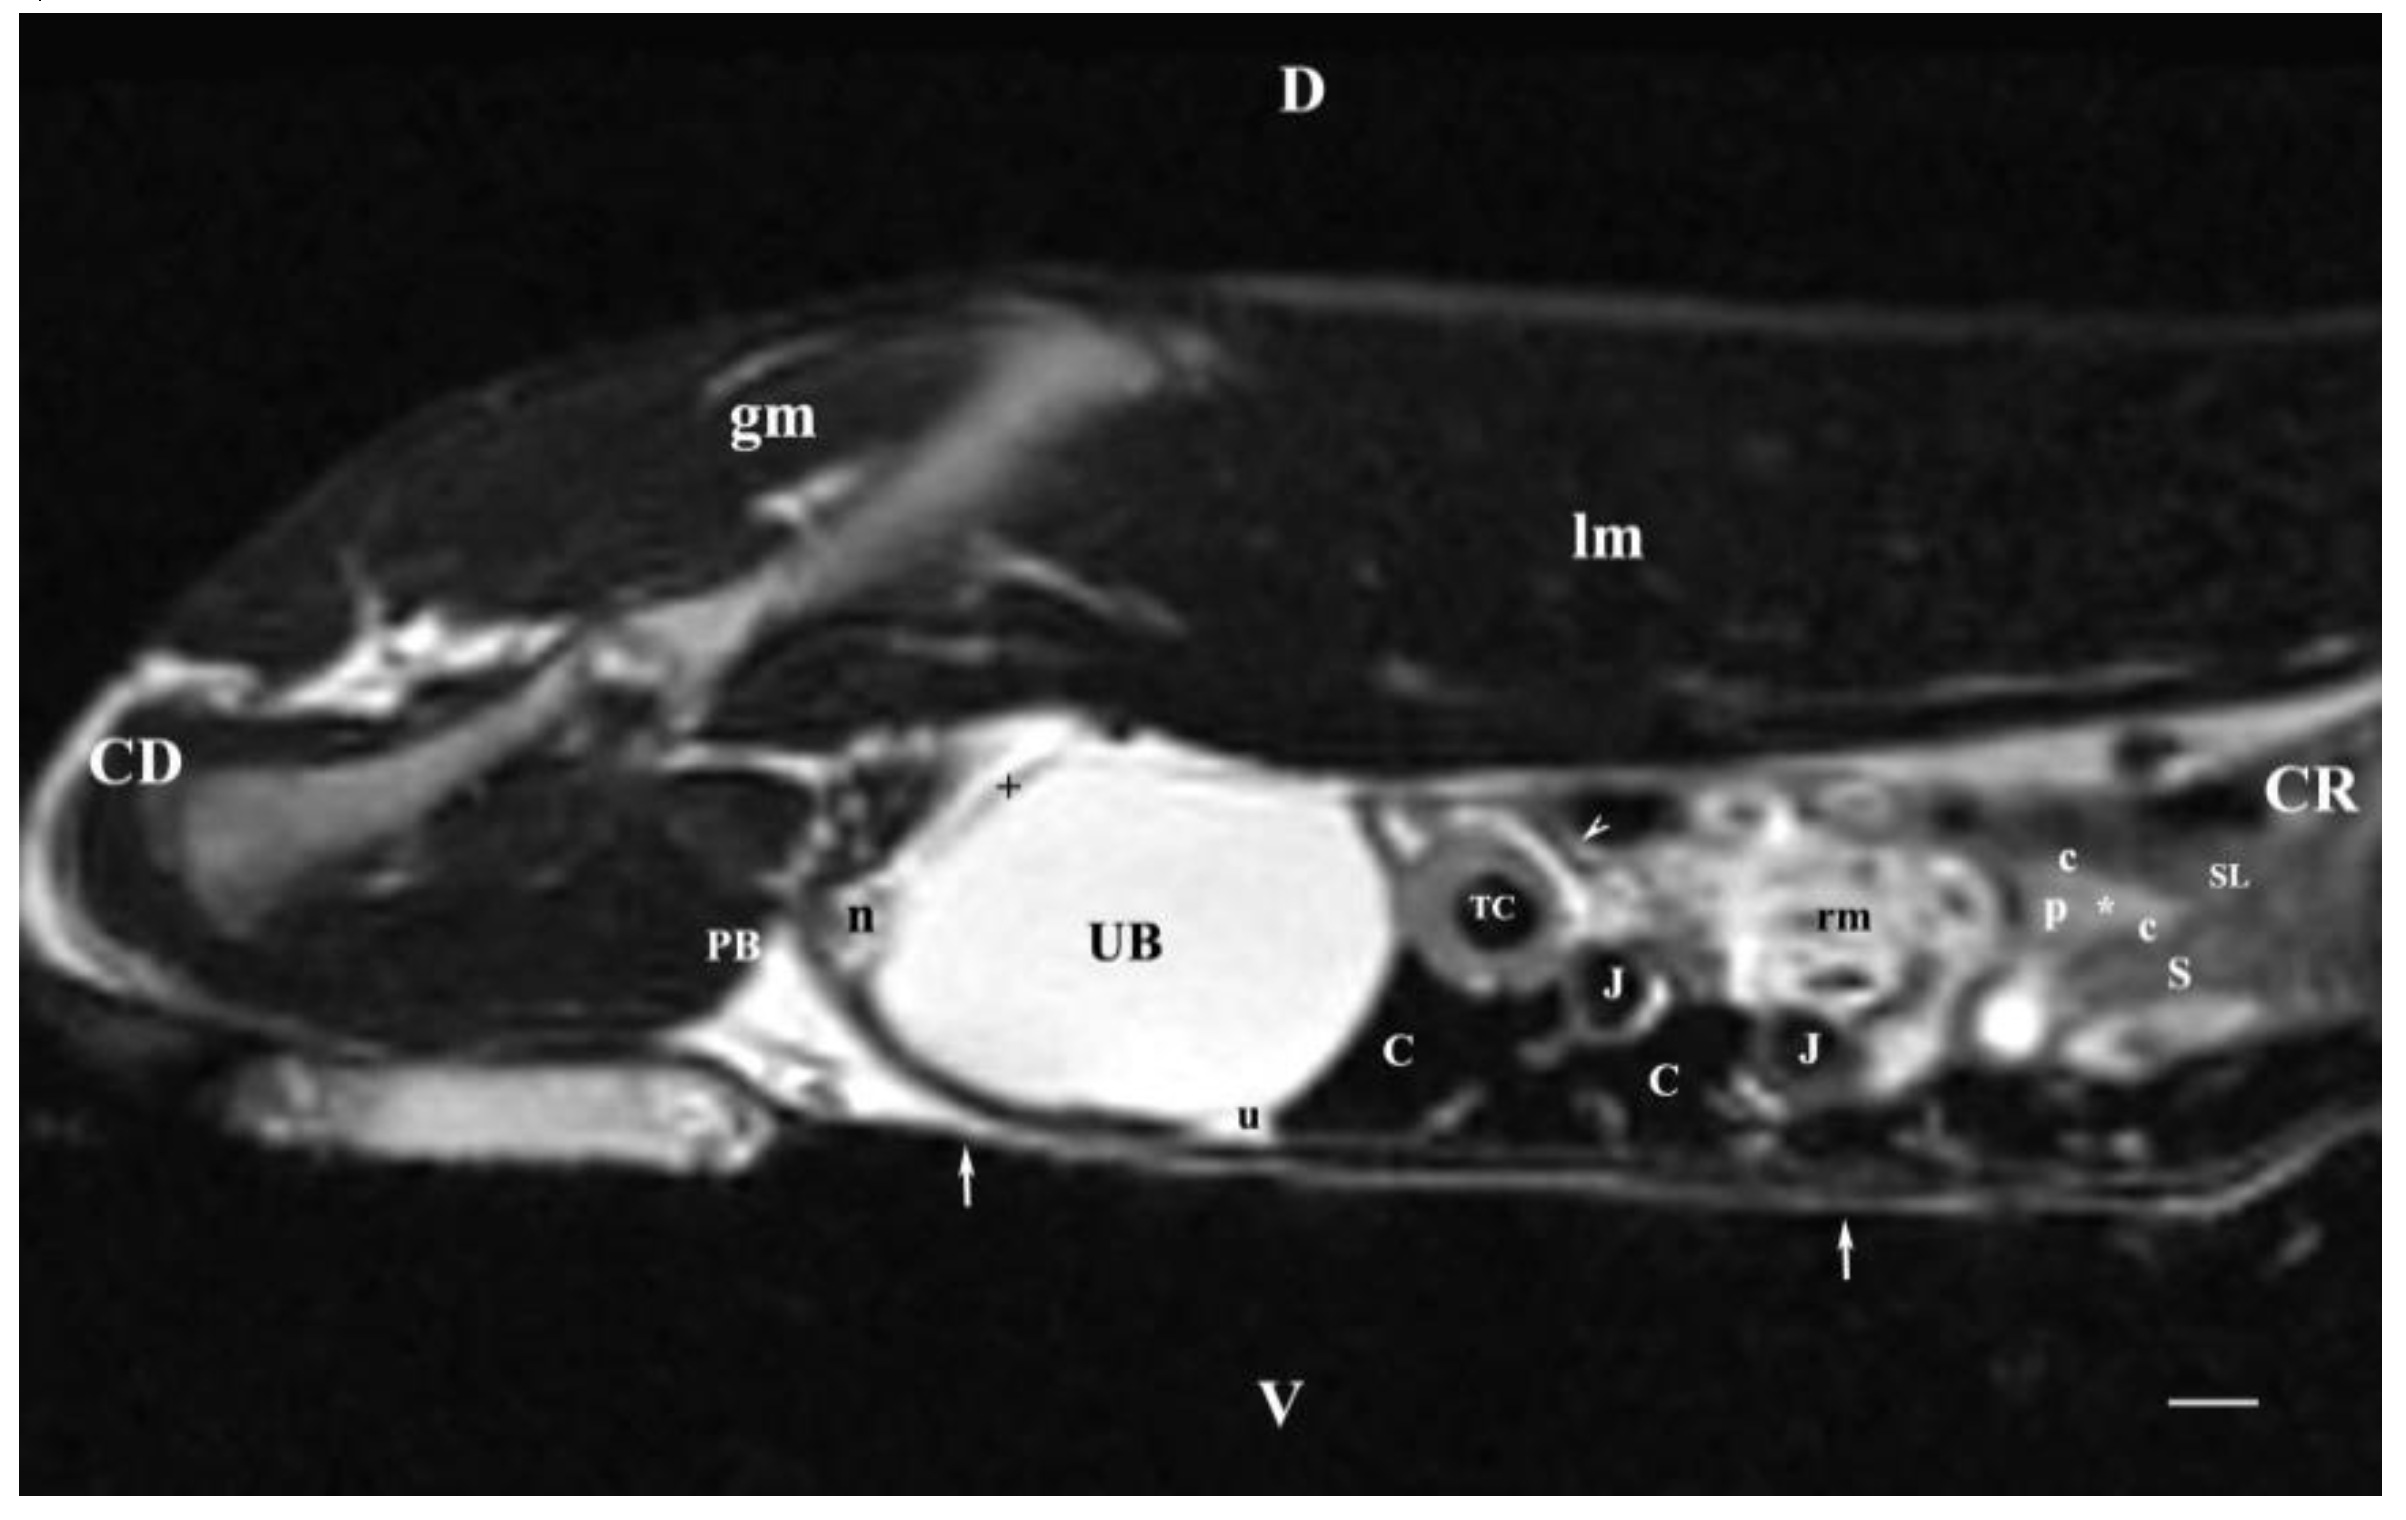

Transverse MRI (Т2-weighted sequence) of organs at the level of the first lumbar vertebra (L1) visualized only the signal characteristics of the right kidney (Figure 1). The latter had an oval, dorsoventrally flattened shape. The renal pelvis was hyper intense and oval. Its borders with the inner part of the medulla were wavy due to the presence of kidney recesses and the irregular relief of crista renalis. The inner part of the medulla was hyper intense compared to the relatively hypo intense image of the outer medulla. The corticomedullary definition was sharply distinguished and outlined the transition between the hyper intense medulla and relatively hypo intense cortex. The fibrous capsule of the right kidney appeared as a thin linear finding. Its intensity was intermediate, compared to the hypo intense cortex and the hyper intense renal adipose capsule. Peripherally and on the right, the right kidney was separated from the hypo intense ventrolaterally located pars descendens duodeni by the adipose capsule. The latter touched the caudate lobe of the liver (Figure 1). Ventromedial to the right kidney was the hypo intense image of the ascending duodenum, whereas the relatively hypo intense image of the caecum was situated ventrally. Dorsal to the right kidney were the hypo intense signals of psoas muscles and longissimus muscle. The left kidney image was not visible, to the left, the heterogeneous hyper intense image of the descending colon, as well as the non-homogeneous hyper intense images of the jejunum and mesentery were visualized (Figure 1).

Transverse MRI (Т2-weighted sequence) at the perpendicular plane through L1 visualized only findings from the right kidney. The image was well defined, and of good morphological informative value. The central part in the kidney soft tissue finding was that of the renal pelvis, whose image was hyper intense due to the selection of T2-weighted sequence. That enhances the signal characteristics of fluid collections (here, urine). Towards the periphery of the renal finding, the intensity of studied structures (inner and outer medulla; cortex) decreased due to reduced tissue hydration. The corticomedullary definition was visible—a sign for intact renal parenchyma.

Figure 1. MRI imaging anatomy of organs from the middle abdominal region (transverse section at the L1 level); R-right; L-left; D-dorsal; V-ventral; (T2-weighted sequence). (C) caecum; (DC) descending colon; (black cross) jejunum; (SP) spleen; (lm) longissimus muscle; (sm) psoas muscles; (rm) root of mesentery; (white star) abdominal aorta; (white cross) caudal vena cava; (black star) renal cortex; (black horizontal arrows) renal medulla; (black line) renal medulla; (black horizontal arrowhead) fibrous capsule; (black point) corticomedullary junction; (c) renal adipose capsule; (CL) caudate lobe; (DD) descending duodenum; (AD) ascending duodenum; (white perpendicular arrow) abdominal wall. Line=10mm.